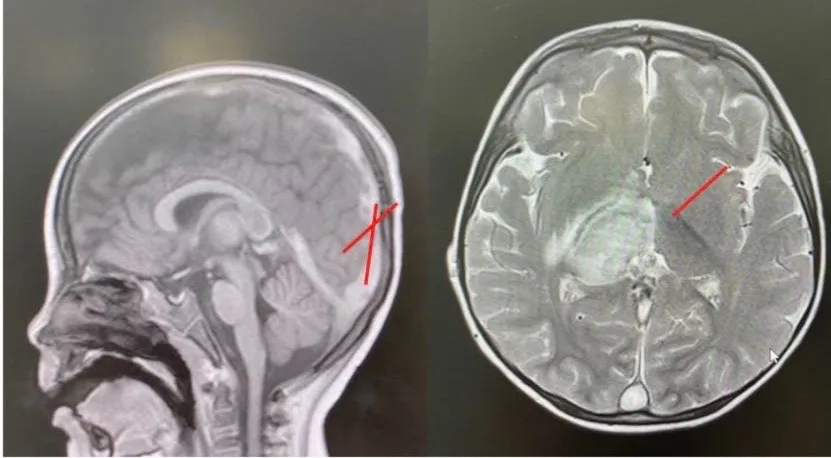

Hình ảnh huyết khối và tổn thương não trên MRI của bệnh nhi

Kết quả chẩn đoán hình ảnh cho thấy tình trạng huyết khối tĩnh mạch nội sọ lan toả, phù não, tổn thương não.